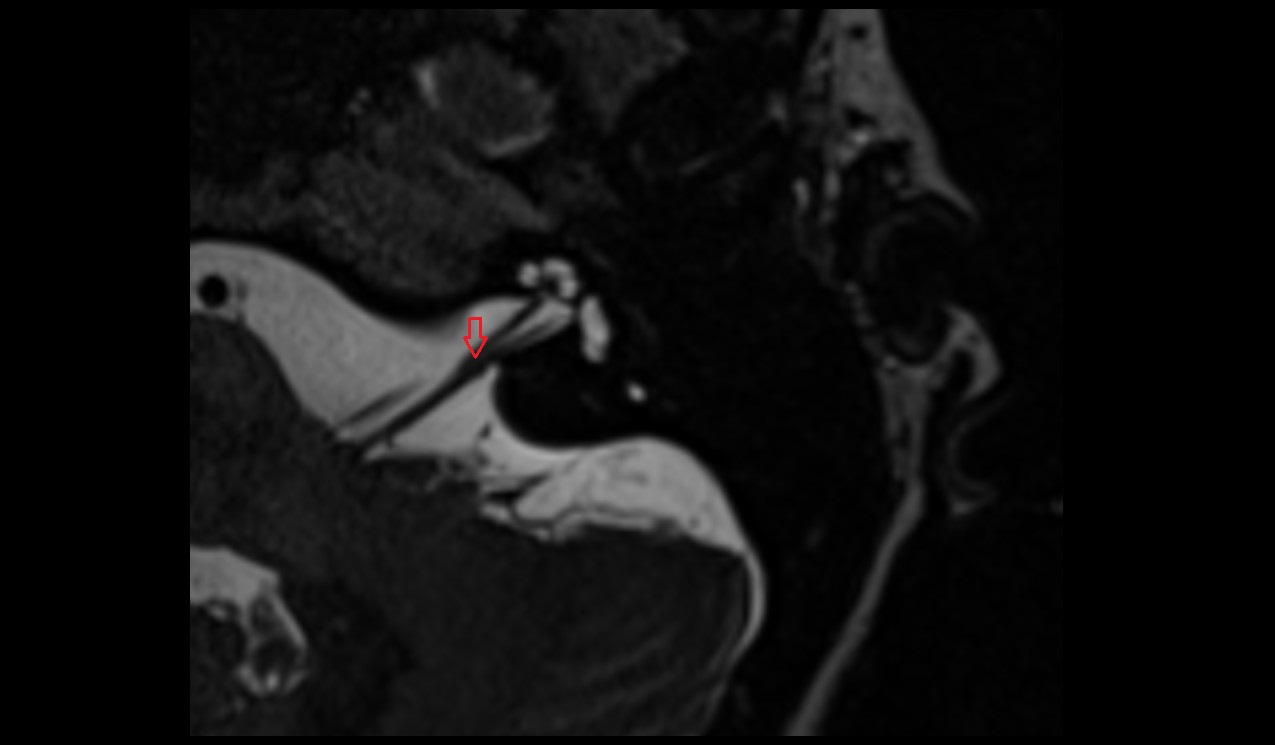

- Articular disc of temporomandibular joint

- Attachment of inferior head of lateral pterygoid muscle

- Attachment of superior head of lateral pterygoid muscle

- Temporomandibular joint

- Mandibular condyle